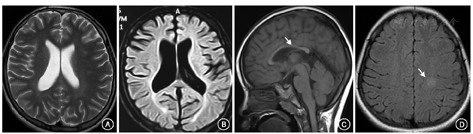

2例新生儿型NPC患者有明显的肝功损害、血胆红素升高、肺炎和肝脾大。8例以神经系统受累为主的患者中,3例出现血小板减少、白细胞减低或全血细胞减少,部分有肝功异常和间质性肺病,均有脾大,3例伴轻度肝大(表1),骨髓检查均发现有泡沫细胞(图1);在初次就诊或其后的随访中,头部MRI示进行性加重的脑萎缩(图2A,图2B),2例有胼胝体变薄(图2C),2例见脑白质区异常信号(图2D)。